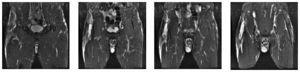

L'estudi ecogràfic va mostrar de nou col·lecció anecoica de 5 × 10 (fig. 2) i la imatge de RM objectivava col·lecció purulenta al terç proximal del múscul tensor de la fàscia lata (fig. 3).

Figura 3 Imatges en STIR en el pla coronal. Es demostren extensos canvis de senyal que afecten el múscul tensor de la fàscia lata dret amb presència d'una col·lecció líquida i abscés de 7 cm de diàmetre longitudinal per 4 y 2,5 cm en el pla transversal. S'observen importants canvis edematosos en la massa muscular, així com la presència d'un important edema en el teixit gras cel·lular subcutani amb petita col·lecció que baixa per la cara anterolateral de la cuixa.